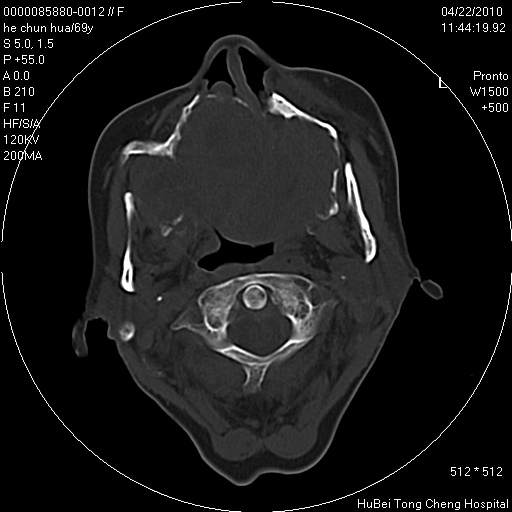

标题: CT25937:女,69Y

硬腭部包块十余年,渐进性增大。